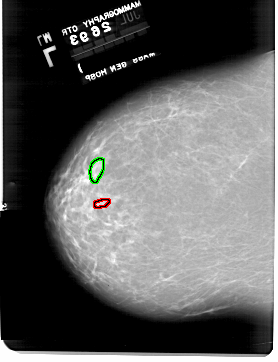

A_1918_1.LEFT_MLO

LEFT_MLO LINES 6871 PIXELS_PER_LINE 4666 BITS_PER_PIXEL 12 RESOLUTION 43.5 OVERLAY

FILE: A_1918_1.LEFT_MLO.OVERLAY

TOTAL_ABNORMALITIES 1

ABNORMALITY 1

LESION_TYPE CALCIFICATION TYPE PLEOMORPHIC DISTRIBUTION CLUSTERED

ASSESSMENT 4

SUBTLETY 2

PATHOLOGY BENIGN

TOTAL_OUTLINES 1

BOUNDARY

ABNORMALITY 2